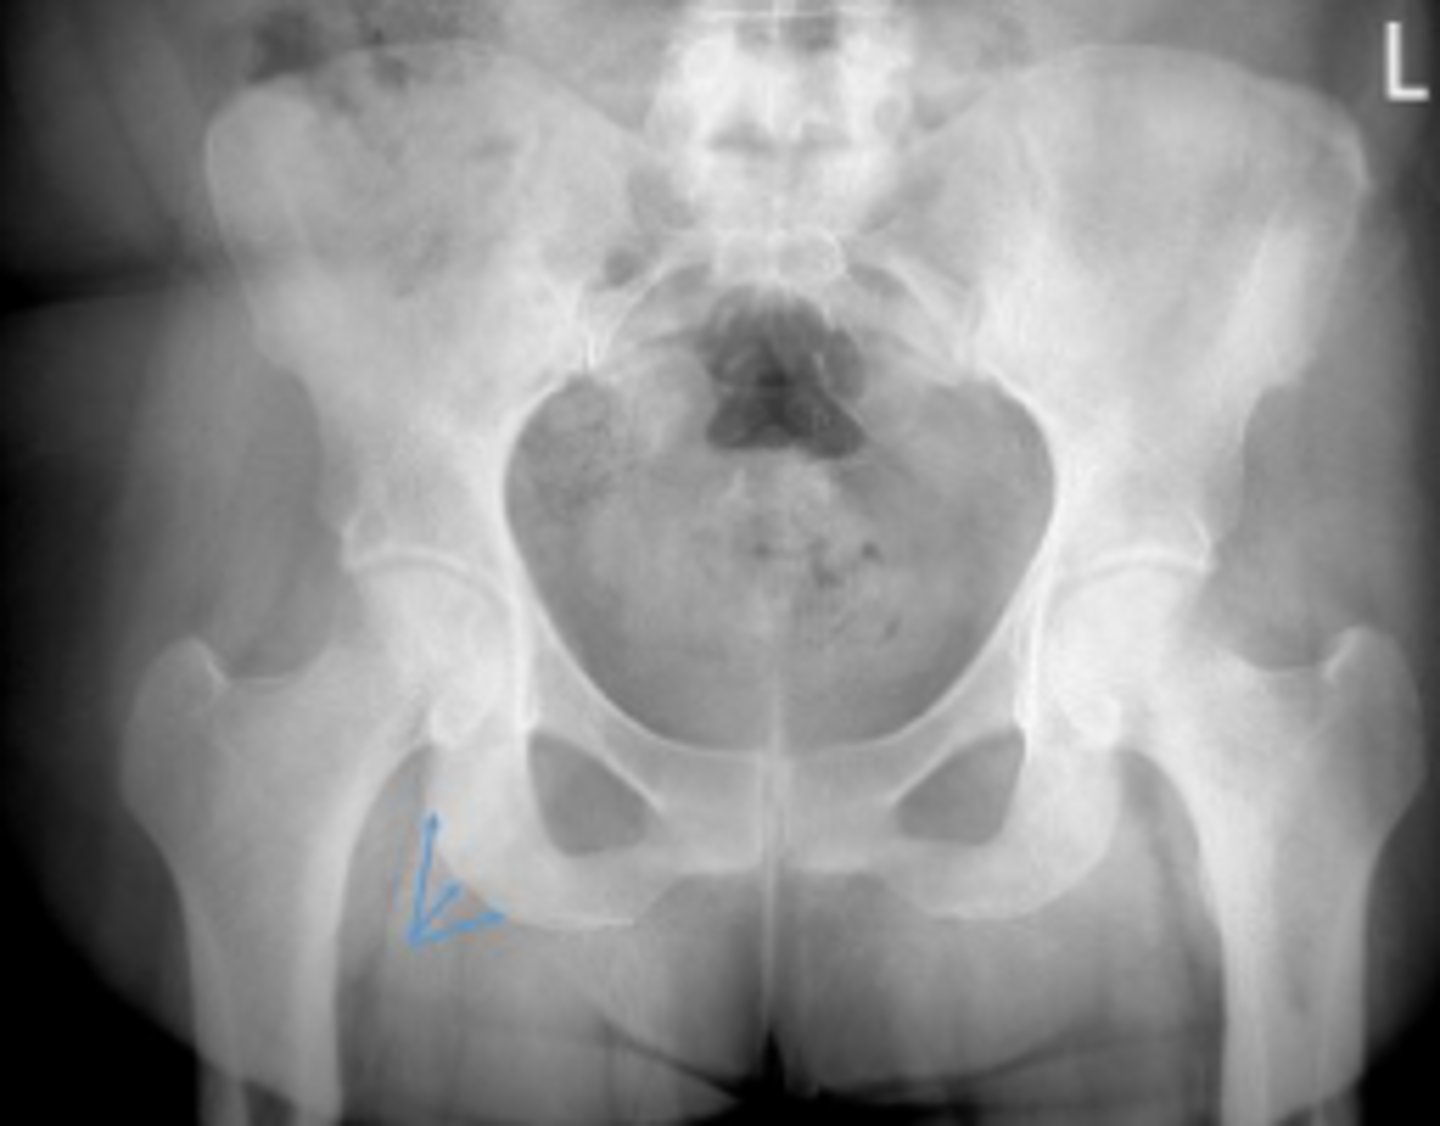

Bilateral frog leg view

What is the name of the radiographic view?

Lesser trochanter of the left femur

What are the arrows pointing to?

Iliopsoas muscle tendon (psoas m. + iliacus m.)

Name 2 structures that are attached to this area?

Left obturator foramen

Left superior pubic ramus

Left inferior pubic ramus

Lesser trochanter of the right femur